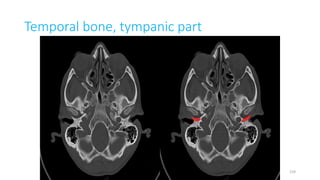

Temporal bone, tympanic part

TYMPANIC PART OF TEMPORAL

TYMPANIC TEMPORAL PART